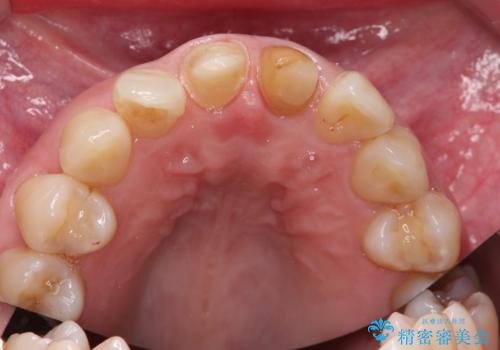

結果、気になっていた色と角度が良くなり、大変喜んでいただけました。

右上1はひっこめた量が大きかったため、反対側の1番と切端をそろえるのに、多少長さは長くなりました。

右上2、左上2の補綴も提案はしましたが、最小限の本数で行っていくことになり、右上2の捻転(歯のねじれ)はそのままとなっております。